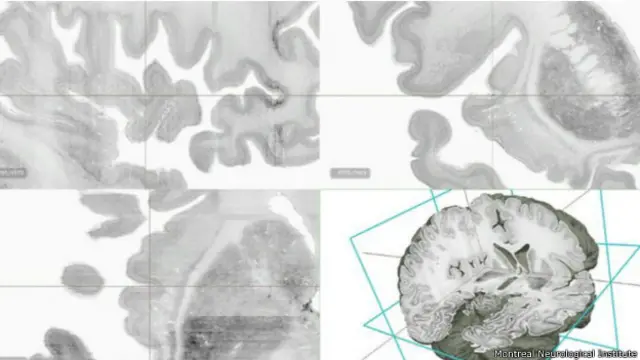

Un grupo de científicos de Alemania y Canadá creó el primer modelo digital en 3D y de alta resolución de un cerebro humano, que han denominado Gran Cerebro.

La reconstrucción muestra la anatomía del cerebro a un detalle microscópico, que le permite a los académicos ver características minúsculas.

Para su creación el equipo de académicos cortó 7.400 secciones en el cerebro de una mujer de 65 años de edad.

Cada una de esas capas tenía la mitad del grosor de un pelo.

Después, tiñeron cada sección para hacer resaltar cada detalle anatómico e hicieron escáneres de alta definición para pasar la información a una computadora.

El paso final fue recomponer digitalmente todas las capas escaneadas.

En total, se capturaron 80.000 millones de neuronas en un minucioso proceso que tomó 10 años.

El resultado es un cerebro digital de alta definición y en 3D en el que los investigadores pueden sumergirse para estudiar áreas de interés con un detalle microscópico.